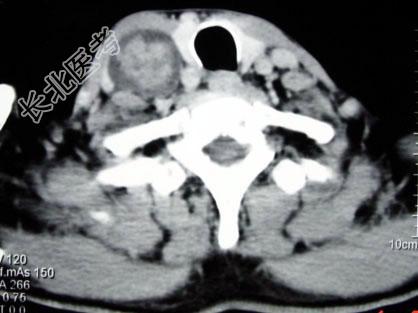

- 多项选择题男,70岁, 右侧颈部无痛性肿块3个月,CT扫描如图所示, 正确的描述或诊断是 ( )

A、右侧颈动脉间隙内见类圆形软组织肿块影,密度欠均匀,边缘光整

B、右侧颈静脉被推压至肿块外后方

C、右侧颈动脉被推压至肿块内后方

D、迷走神经源性肿瘤

E、交感神经源性肿瘤